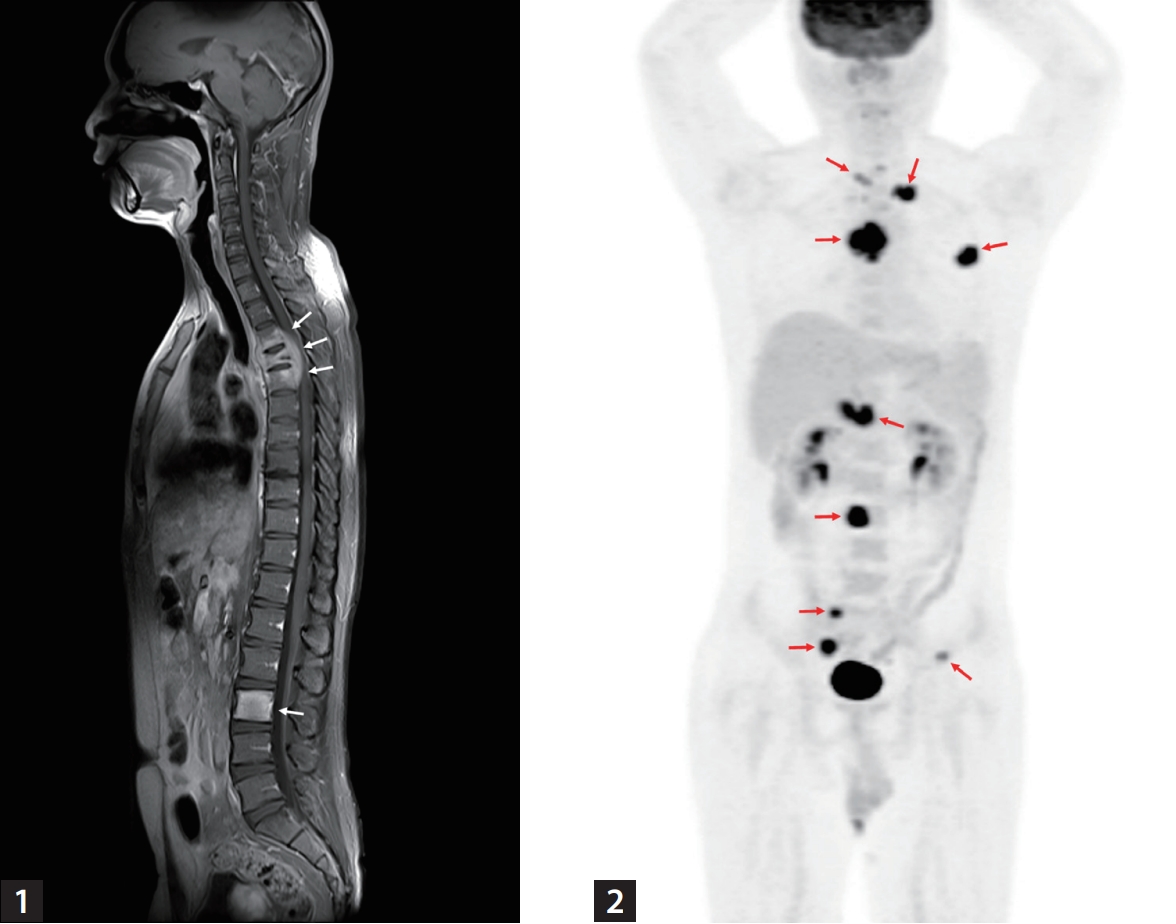

A 32-year-old man without underlying diseases presented to the emergency department with an abrupt onset of gait disturbances and a 4-week history of back pain. The patient was afebrile, and all laboratory findings were normal. Rapid plasma reagin test for syphilis was negative. Whole-spine magnetic resonance imaging revealed an abnormal signal intensity with contrast enhancement at levels T3-T5 and level L3 (Fig. 1), as well as in the right sacral alar portion and left second rib (not shown). However, chest computed tomography (CT) showed no abnormalities in the lung parenchyma, airways, pleura, or lymph nodes. Bone scan suggested bone metastases in the skull, left clavicle, left third rib, and T3-T5 and L3 vertebrae. 18F-fluorodeoxyglucose (18F-FDG) positron emission tomography/CT showed intense FDG uptake in multiple bone lesions and portocaval areas, possibly bone metastases and metastatic lymphadenopathy (Fig. 2). Percutaneous transpedicular bone biopsies were performed in the T4 and L3 vertebral bodies. Histopathological findings revealed chronic granulomatous inflammation with necrosis; however, acid-fast bacilli staining and duplex real-time polymerase chain reaction for Mycobacterium tuberculosis complex and non-tuberculous mycobacteria from fresh bone tissue were negative. On the fifteenth day after the biopsy, the mycobacterial culture from the bone specimens tested positive for M. tuberculosis complex.